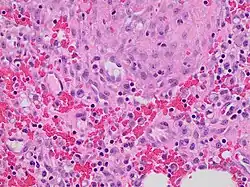

Granulation tissue is new connective tissue and microscopic blood vessels that form on the surfaces of a wound during the healing process.[1] Granulation tissue typically grows from the base of a wound and is able to fill wounds of almost any size. Examples of granulation tissue can be seen in pyogenic granulomas and pulp polyps. Its histological appearance is characterized by proliferation of fibroblasts and thin-walled, delicate capillaries (angiogenesis), and infiltrated inflammatory cells in a loose extracellular matrix.

The main immune cells active in the tissue are macrophages and neutrophils, although other leukocytes are also present.[6] These work to phagocytize old or damaged tissue, and protect the healing tissue from pathogenic infection. This is necessary both to aid the healing process and to protect against invading pathogens, as the wound often does not have an effective skin barrier to act as a first line of defense.

In vascularisation, also called angiogenesis, endothelial cells quickly grow into the tissue from older, intact blood vessels.[8] These branch out in a systematic way, forming anastomoses with other vessels.